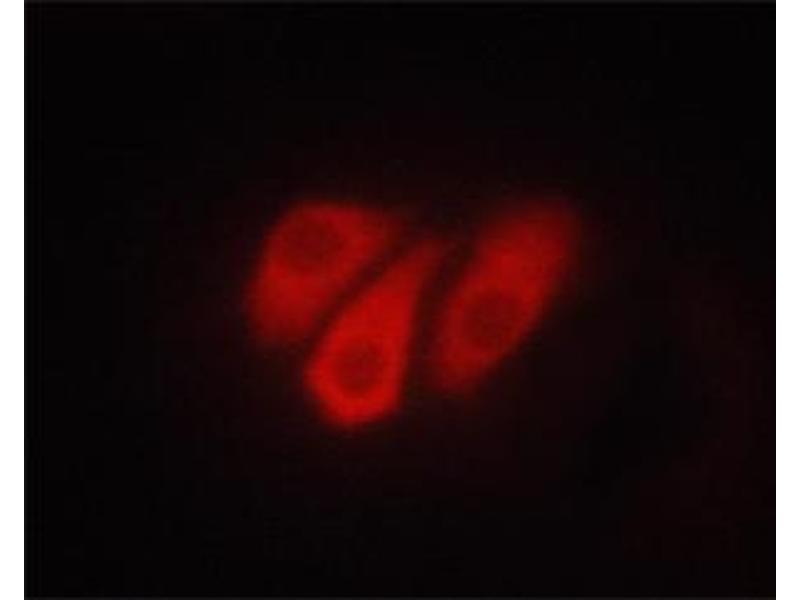

ATP1A1 Antikörper (pSer23)

Der Kaninchen Polyklonal anti-ATP1A1 Antikörper wird verwendet zum Nachweis von ATP1A1 in Proben von Human, Ratte und Maus. Er wurde validiert für WB, ELISA, IF und ICC.

Western Blotting (WB), ELISA, Immunofluorescence (IF), Immunocytochemistry (ICC)

pSer23

Phospho-ATP1A1 (Ser23) Antibody detects endogenous levels of ATP1A1 only when phosphorylated at Serine 23.

WB 1:500-1:2000, IF/ICC 1:100-1:500, ELISA(peptide) 1:20000-1:40000